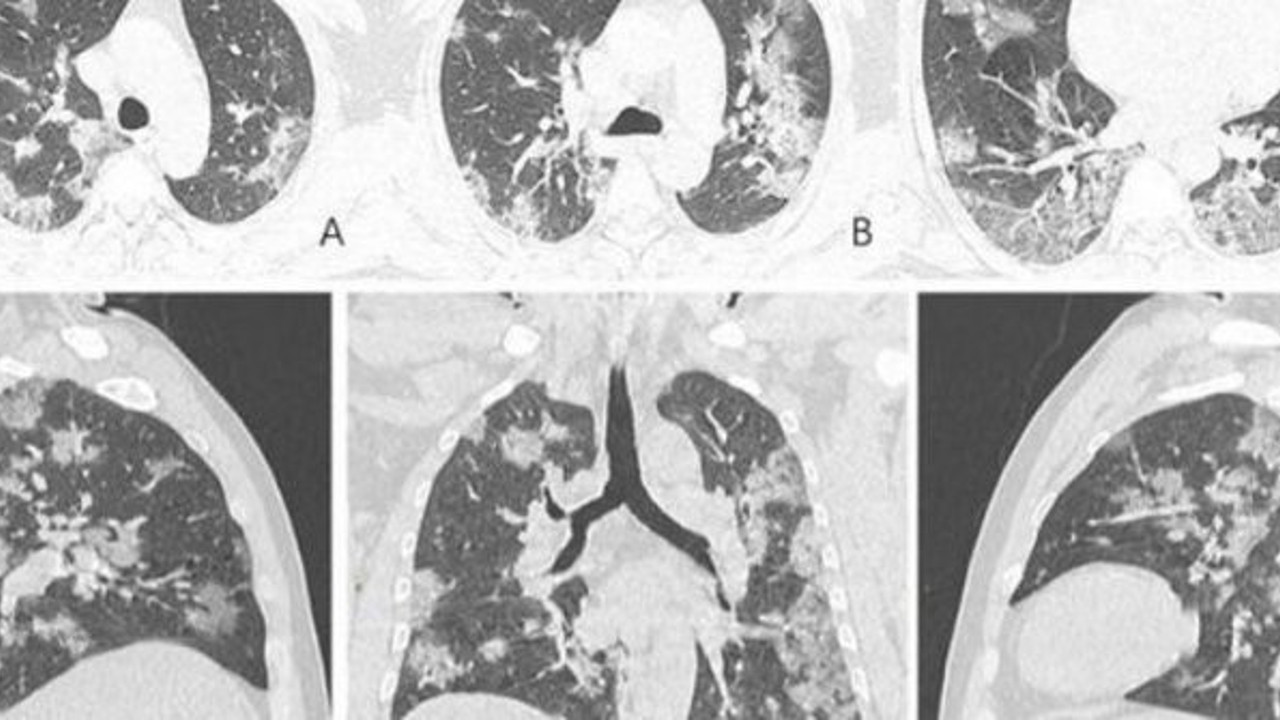

Kuzey Amerika Radyoloji Derneği (RSNA) 44 yaşında corona virüsten ölen bir erkek vakanın akciğer röntgen fotoğraflarını yayınladı. Röntgen filmlerinde akciğerlerin çevresindeki sıvının nasıl zamanla daha belirgin ve yoğun bir hale geldiğini gözler önüne seriyor.

Çin vatandaşı hastanın yaklaşık iki hafta boyunca ateş ve öksürükten şikayetlerinin ardından sonra 25 Aralık 2019'da hastaneye kaldırılan hastaya doktorlarilk olarak zatürre ve akut solunum sıkıntısı sendromu teşhisinde bulundu. Hasta tedavi edilmesine rağmen 1 hafta sonra corona virüse bağlı semptomlar nedeniyle yaşamını yitirdi.

AKCİĞERDEKİ BEYAZ LEKELER DİKKAT ÇEKİYOR

Corona virüs hastalarının çoğunda ters bir çember işareti belirgin bir şekilde göze çarpıyor. Akciğerlerin alt köşelerindeki beyaz lekeler virüsün varlığını gözler önüne seriyor.